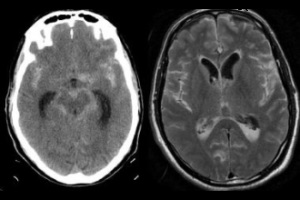

Темой очередного заседания неврологического общества г. Киева стала одна из наиболее насущных проблем неврологии и медицины в целом – вторичная профилактика инсульта.

В мире ежегодно регистрируется около 15 млн инсультов, в связи с инсультами умирают более 5,5 млн человек.

Качество медицинской помощи при инсульте может и должно быть улучшено – об этом говорят значительные различия показателей ежегодной заболеваемости и смертности в разных странах мира. Несмотря на то что в большинстве развитых стран действуют национальные..

В последние годы во всем мире прогрессивно возрастает количество мозговых инсультов (МИ), в первую очередь за счет ишемических нарушений мозгового кровообращения. В ближайшие десятилетия эксперты ВОЗ предполагают дальнейший рост количества ишемических...

Медико-соціальне значення проблеми судинних захворювань нервової системи визначається високою питомою вагою їх у структурі захворюваності та смертності населення, високими показниками первинної інвалідності. З-поміж усіх судинних захворювань головного...

Перечень состояний, при которых имеются нарушения основных когнитивных функций, весьма широк. Он включает в себя когнитивный дефицит при травме мозга, инсультах, хронической цереброваскулярной недостаточности, поражениях мозга нейродегенеративного...